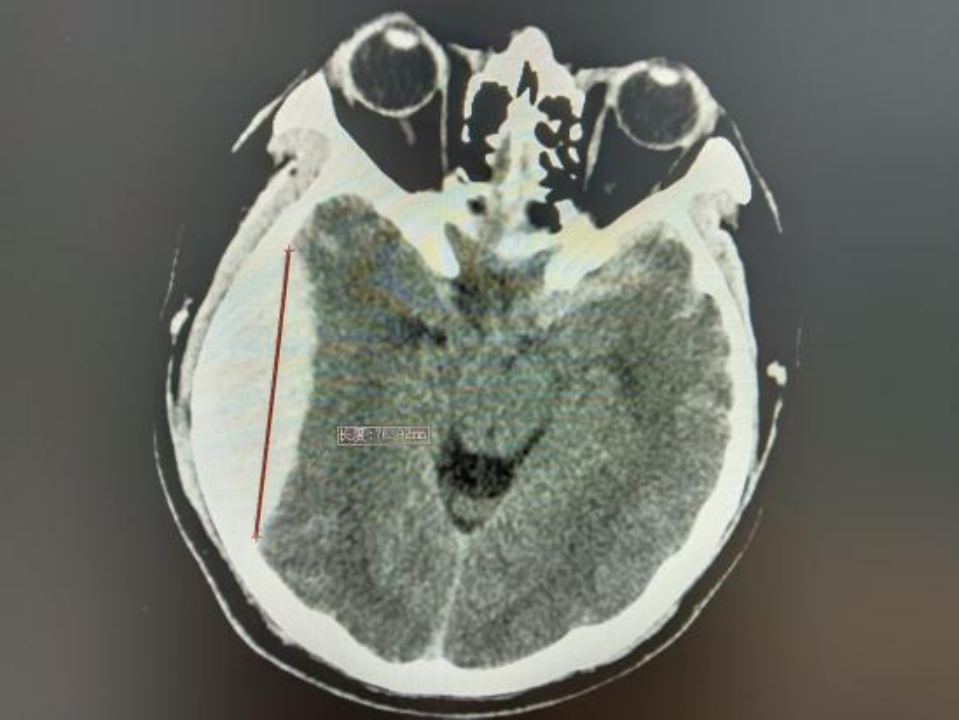

△术前颅脑CT

近期,北大人民青岛医院神经外科团队在北京大学人民医院神经外科专家刘波带领下,常态化开展神经内镜下硬脑膜外血肿清除术。其中一位19岁的年轻小伙,驾驶摩托车不慎摔伤,伤后头痛、头晕、恶心,头痛呈进行性加重,逐渐开始出现意识障碍,到青岛医院急诊行颅脑CT检查后证实为创伤性硬脑膜外血肿,神经外科团队予以急症状态下神经内镜下硬脑膜外血肿清除术手术治疗,目前患者已经康复出院。